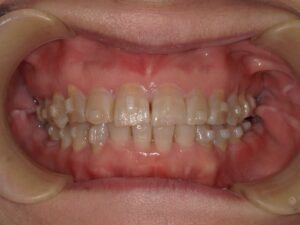

初診時54歳女性 体に不調を感じるとのことでした。夜間熟睡ができない。若い時は肩こりや頭痛もあった。左でよく噛んでいる。ということでした。口腔内を拝見すると下の前歯の真ん中が少し左にずれていました。かみ合わせた時に下の前歯は上の前歯に少し覆われるのが一般的なのですが、半分以上隠れています。歯科用語では過蓋咬合と言います。かみ合わせた時に下の前歯が上の前歯で完全に覆われている方もいらっしゃいます。下の前歯の付け根当たり、犬歯がわかりやすいかもしれません。骨がもっこりしているように見えます。かみ合わせが強い方によく見られます。骨隆起と言います。上の真ん中から3番目の犬歯が一つ後ろの歯に比べて内側に傾斜しています。

歯並びの不正も少しあります。

前歯4本が直線的に並んでいます。真ん中から2つ目と3つ目の間に段差がついているような感じです。顎が少し小さくて歯が並ぶだけの大きさになっていないようです。

下の前歯にがたつきがあります。奥歯が内側に倒れています。向かって左の奥から3番目、4番目がわかりやすいですが、奥歯は全部そうなっています。舌が写っていますが、窮屈そうにみえます。前歯が並ばないことから顎が少し小さいこと、歯が内側に傾斜していることで、舌の置き場が狭いのです。舌は行き場をなくすと奥に行くか、下にいくしかありません。そうなると気道が狭くなります。人は呼吸しないと生きていけませんから気道を確保するために首を突き出すような姿勢をとります。姿勢が悪くなる原因となります。無理な姿勢を維持するので、適正な筋肉の使い方でなくなります。肩こり、首の凝り、腰痛など全身はつながっています。かみ合わせのズレや不正咬合から離れた部位に不具合が出現する可能性があるというのはこういうことなのです。

かみ合わせの高さが低くなるにつれ、噛む筋肉は強く作用する。

前歯のてっぺんがすり減っているのもわかると思います。本来犬歯は山のように先端が少し尖っているのですが、平らになっています。これは噛みしめてすり減っているか、歯ぎしりしていることが考えられます。たいていの方はそんなことはない、家族にも言われたことがない、など強く否定されます。でも痕跡はあります。では何故噛みしめるのでしょうか。顎は上顎が先に大きくなり、そのあとから下顎が大きくなるという成長過程をとります。上顎が適正に大きくならないと、後から成長する下顎が前への成長がブロックされます。上の前歯に下の前歯が当たってしまうと下顎は後ろに下がります。下がると気道が狭くなり、苦しいので本能的に前に出そうとします。また奥に下顎が下がるとかみ合わせの高さが低くなってしまいます。かみ合わせが低くなると筋肉は強く作用します。成長期に適正に顎が大きくなれず、その時期を過ぎて不正咬合のままであることが気道を狭くしたり、噛む筋肉を強く作用させてしまうことが噛みしめや歯ぎしりの理由ではないかと考えています。エラの張りもかみ合わせの高さが低くなって筋肉が過緊張を繰り返し、変な言い方ですが鍛えられていった結果で起こります。噛み合わせの低い方に噛み癖があります。顔の傾きや顎にズレが出ます。加齢によるすり減りだけでは根拠が薄いのです。